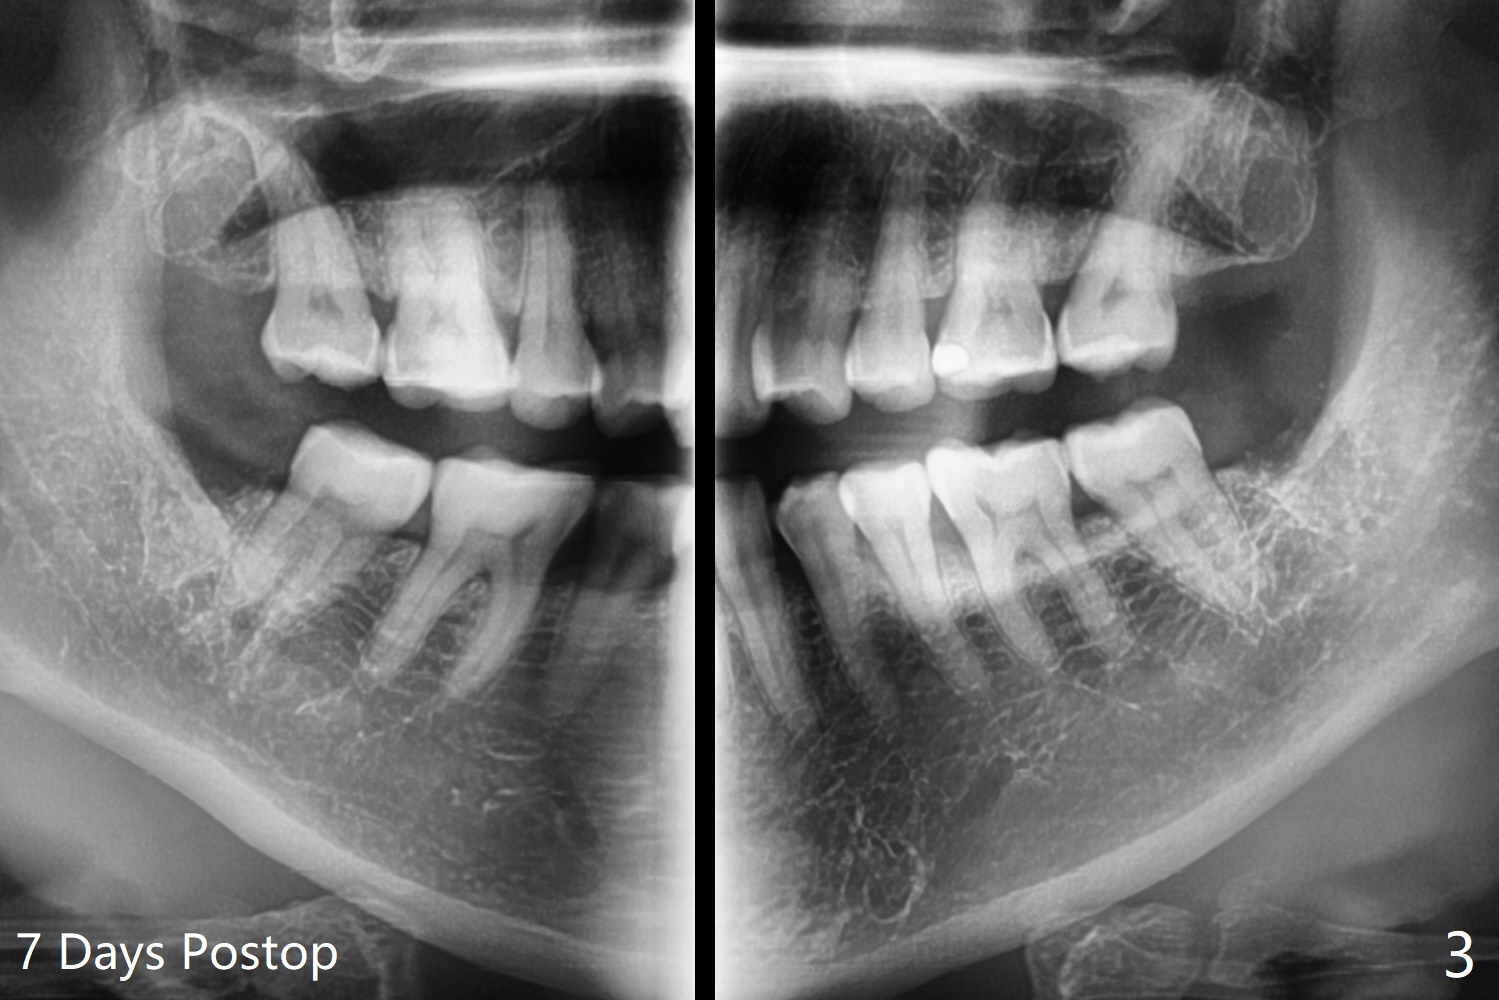

51岁女年终有多余的钱,想拔除左下智齿(早期龋齿),经过讨论,也同意拔除右下和左上智齿(图一)。看上去所有智齿拔除容易,但是右下第二,三磨牙之间骨板薄,不敢使用牙挺,怕的是松动第二磨牙,而单纯使用牙钳无法松动智齿,只好切开,颊侧去骨,形成purchase point,牙齿顺利拔除。左下智齿也采取同样方法拔除,之后下颌牙槽窝放置0.5毫升Bond Apatite和半块胶原塞,PGA多针缝合(图二),术后口服Amoxicillin。术后第四天左下出现典型干槽症症状,第七天就诊,缝线溶解,牙槽窝似乎是空的,生理盐水冲洗,改善不大,而右下缝线仍在,伤口愈合正常。拍摄局部全景片(图三),左下牙槽窝上半部好像失去骨水泥。疑问:局麻下,再次清创,放置粘性骨粉和PRF膜,能改善症状?伤口需要减张缝合(第一次和这次,periosteum underscoring)?